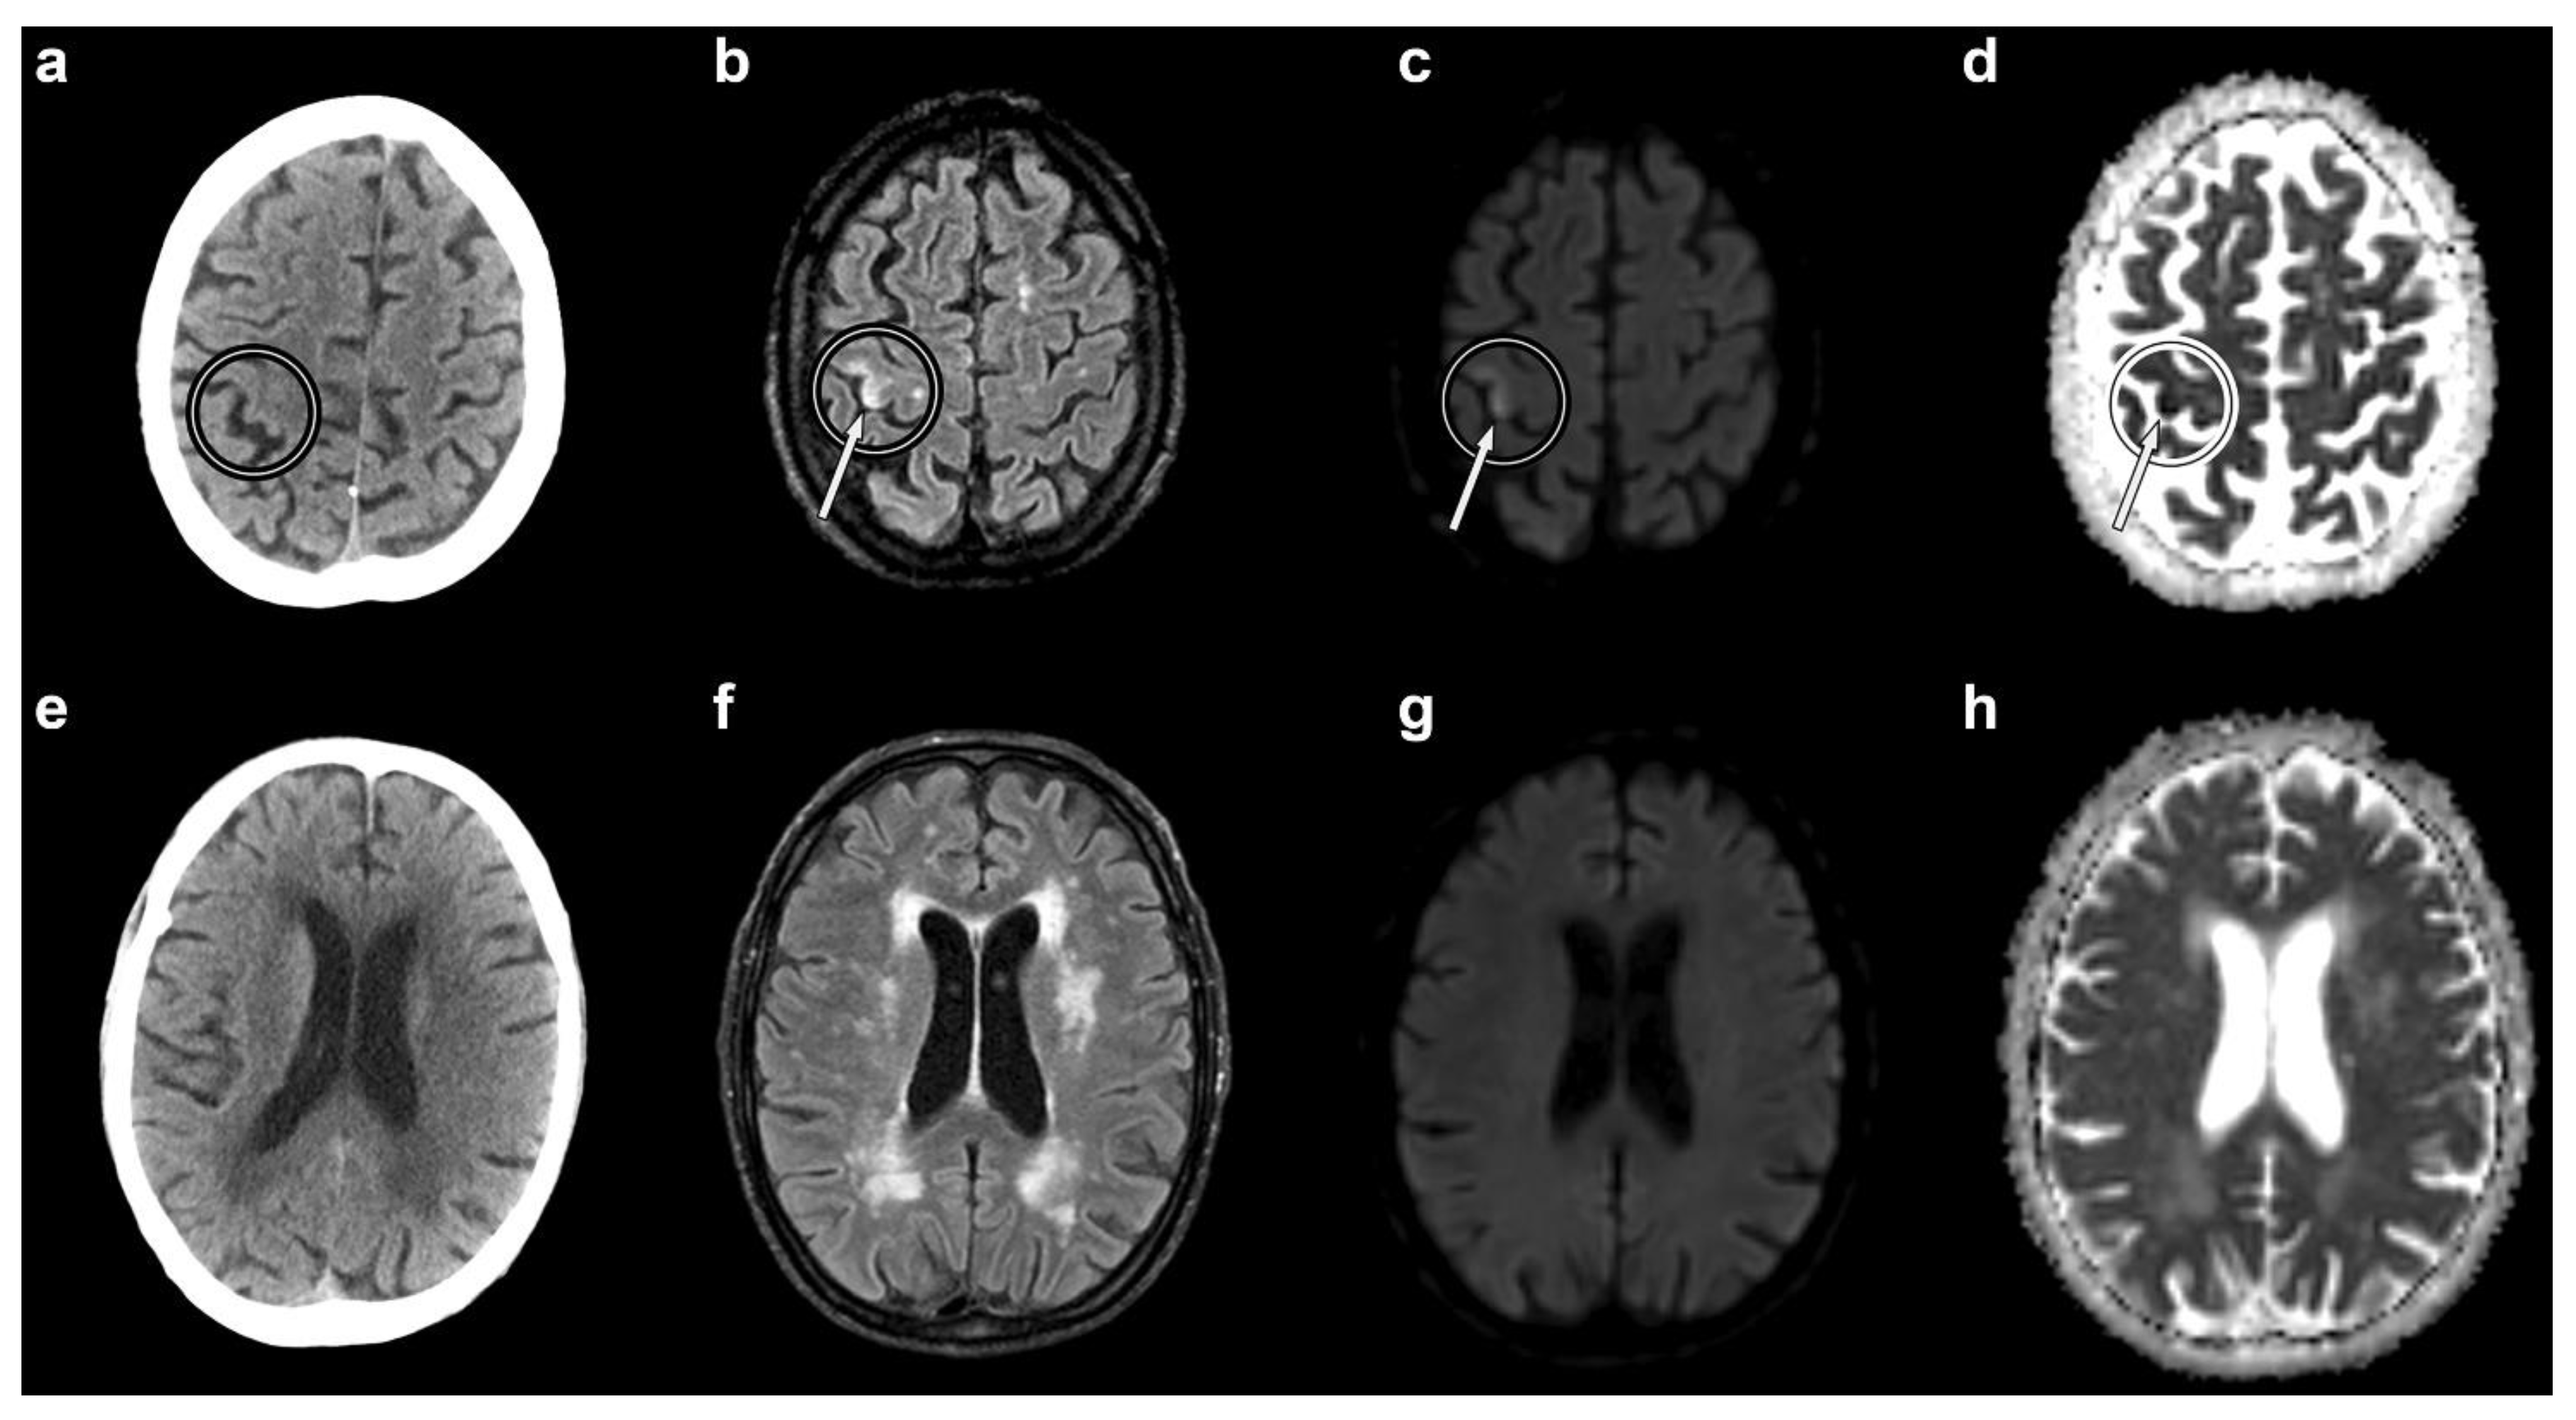

Within a few minutes from the end of the manoeuvre, he became briefly unconscious and, on regaining consciousness, complained of left upper-limb weakness. His neurological examination was normal and his vital signs were unchanged from previous assessments (blood pressure of 110/60 mmHg, heart rate of 50 bpm, oxygen saturation of 97% on room air). He was therefore maintained under observation. One hour later, he reported sudden-onset weakness of the left hand with wrist drop. Neurological examination showed an isolated flaccid paresis of the left hand. Although he complained of hand numbness, there was no objective evidence of sensory deficits. He was administered 100% oxygen and was referred for an urgent non-contrast brain CT scan. The latter was performed 45 min after the onset of hand paresis, and it excluded haemorrhage, early ischaemic changes, and other possible causes of stroke (Figure 1a). The patient was started on antiplatelet treatment (aspirin 100 mg/daily) and the planned liver biopsy was suspended. Non-contrast brain magnetic resonance imaging (MRI) was obtained the next day, about 22 h after the onset of hand paresis. It showed a recent ischaemic lesion of the right superior precentral gyrus (Figure 1b–d). Both CT and MRI displayed diffuse chronic cerebrovascular disease (Figure 1e–h).

Figure 1. Non-contrast axial brain computed tomography (CT) and magnetic resonance imaging (MRI) scans. Circles indicate the right “hand-knob” area (horizontal epsilon-shaped). CT shows no evidence of cerebral air bubbles (a). The MRI fluid-attenuated recovery (b), diffusion-weighted (c), and apparent diffusion coefficient (d) sequences demonstrate a recent ischaemic lesion of the lateral portion of the right “hand-knob” area (arrows). Both CT and MRI show diffuse chronic cerebrovascular disease (lower panel: (eh)).